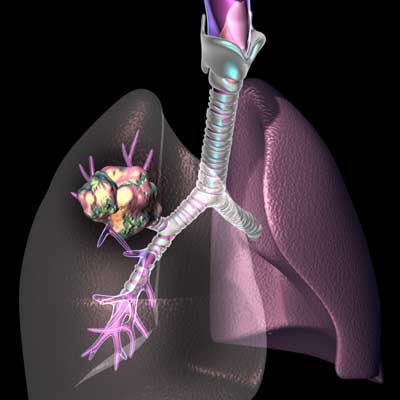

El cáncer pulmonar es uno que se forma en los tejidos pulmonares. Según la apariencia celular, esta patología se puede clasificar en dos tipos: células pequeñas y no células de células, y más agresivo es un peor pronóstico que las células pequeñas.

Los principales síntomas que ayudan a detectar el cáncer de pulmón son toser o saltar en sangre, infecciones respiratorias recurrentes, dolor de hombro, espalda o pecho, dificultades respiratorias, rumores, silbato en la respiración, fatiga, debilidad general y pérdida de apetito. Dadas estas señales de advertencia, es necesario ir al médico. El diagnóstico temprano más grande es la supervivencia “, dice Ávila Vivas.

El neumonólogo afirma que la cirugía más común, la radioterapia y la quimioterapia son. El primero se aplica en su etapa temprana. Elimina el tumor y cualquiera de los ganglios linfáticos que pueden contener células cancerosas. La radioterapia utiliza grays x para dañar las células malignas y detener su crecimiento o multiplicación, y la quimioterapia viaja a través del cuerpo, influyendo en las células cancerosas en cualquier lugar, a diferencia de la cirugía y la radioterapia, con la cual se resuelve el tratamiento local de la enfermedad. “Otro procedimiento es la inmunoterapia que, en lugar de atacar directamente las células, ayuda al sistema inmunitario del cuerpo a reconocerlas y destruirlas”.